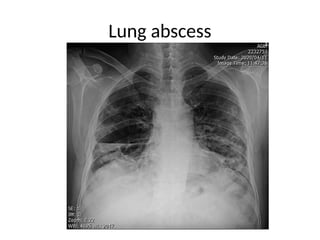

Lung abscess

• Lung abscess is defined as necrosis of the

pulmonary tissue and formation of cavities

containing necrotic debris or fluid caused by

microbial infection. The formation of multiple

small (< 2 cm) abscesses is occasionally

referred to as necrotizing pneumonia or lung

gangrene.